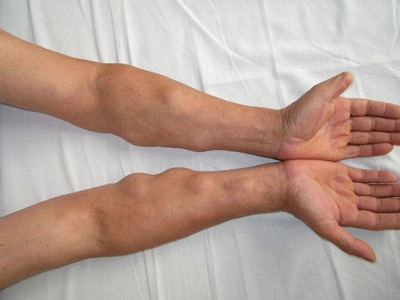

肌肉条索状结节

临床上可表现为出现多发的坚硬结节,结节可互相融合形成条索状,看着像